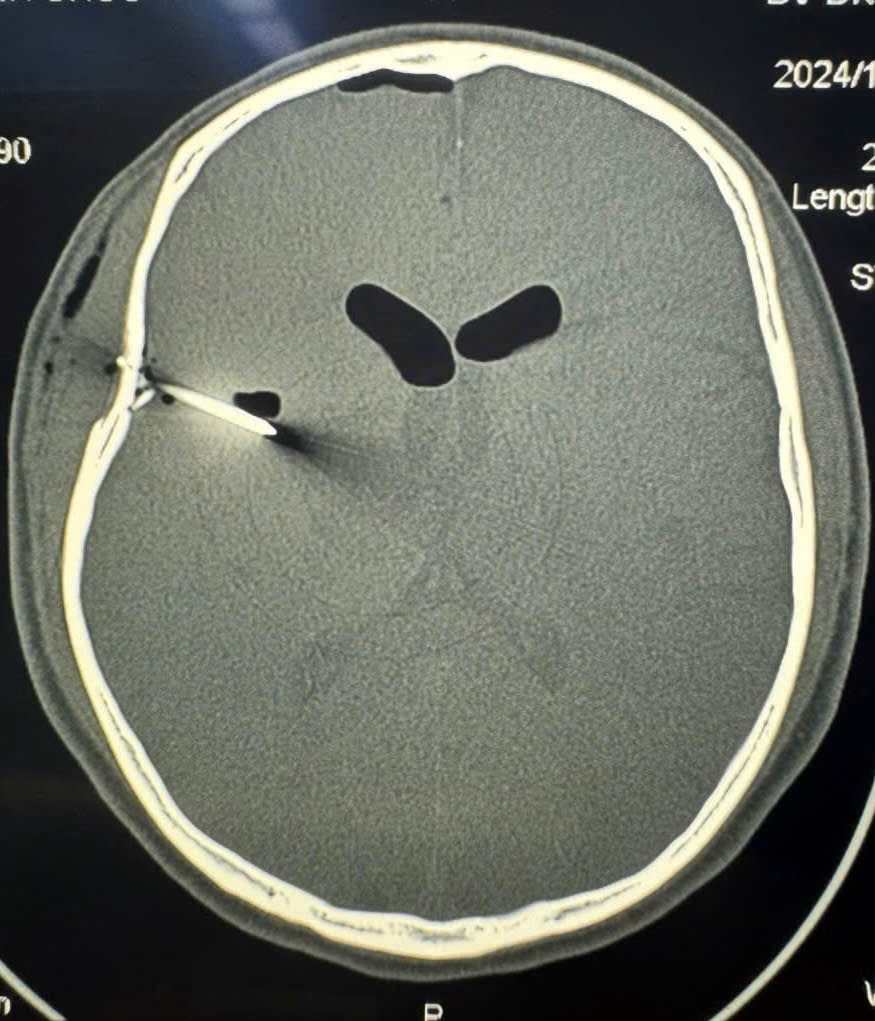

Saving a patient whose skull was pierced by a nail gun

108 Central Military Hospital has just admitted a 38-year-old male patient with an open brain wound with an iron nail piercing through the skull.